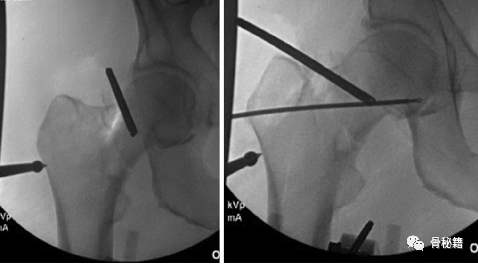

术中撬拨复位

应用Schanz 针撬拨和以经皮的顶棒来进行复位

复位后应用克氏针临时固定